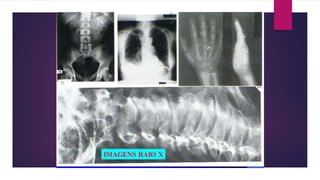

RAIO X SIMPLES

O feixe de Raio X passa pelo paciente que está

posicionado sobre um chassis, impressionando o filme

dentro da placa, com diferentes tonalidades, de

acordo com a penetração dos raios.

As tonalidades são dependentes da espessura e da

densidade da estrutura que está sendo atravessada.